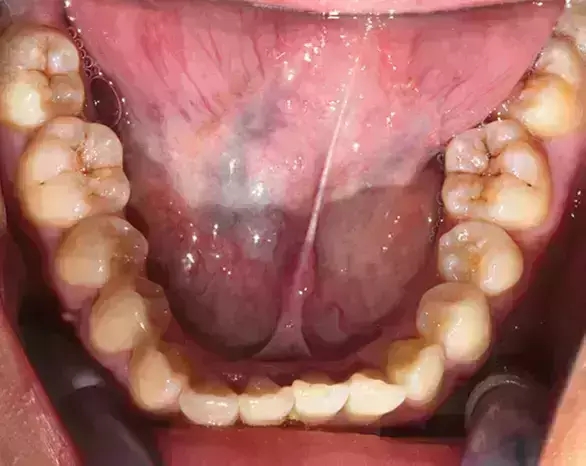

Damon 病例分享:安氏 II 類二分類露齦笑的矯治(董一磊)

治療前后對比